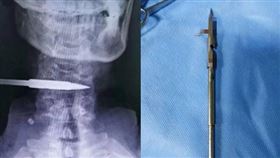

捕魚手滑…「1根標槍」射進他脖子

外出釣魚、捕魚是一項有益身心的活動,沐浴在大自然的懷...